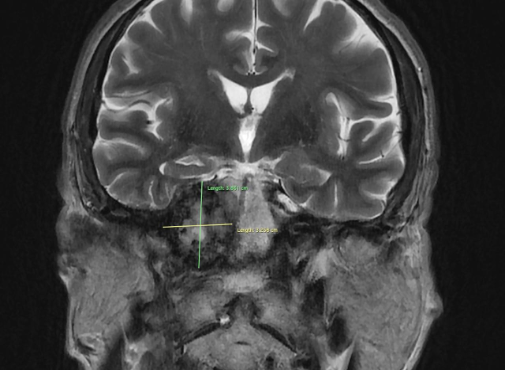

Results: Brain MRI (1,5 Tesla): MRI of the brain demonstrates a lesion in the right temporal bone region (squoma part) with mass effect on adjacent structures. The lesion measures (38х25х33 cm) and exhibits characteristics suggestive of a space-occupying process. Findings include: possible involvement of the brainstem and surrounding neurovascular structures, no evidence of acute hemorrhage, hydrocephalus, or significant midline shift.

Frontal